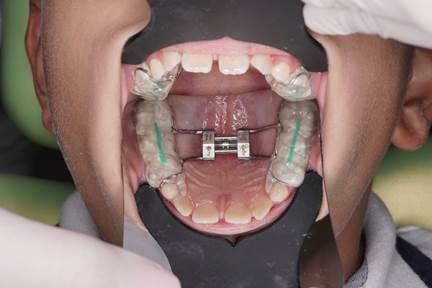

Durante el tratamiento (vista superior): Colocación de un disyuntor de McNamara adaptado con pistas directas para guiar la función masticatoria y estimular un desarrollo óseo equilibrado.